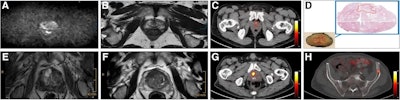

Axial views of exemplary case studies in which additional PSMA PET/CT changed prostate cancer (PCa) management. (A–D) A 68-year-old man with isolated PSA elevation had no tumor-suggestive findings on mpMRI (A and B), but they were high suggestive of PCa on PSMA-PET/CT (C). After radical prostatectomy, 22-mm index tumor identified on PSMA- PET/CT was confirmed with Gleason score of 7a (D). Reviewers without PSMA-PET/CT information (MRI-only pathway) recommended continued PCa screening, whereas reviewers with PSMA PET/CT knowledge suggested active treatment. (E–H) A 72-year-old man with PSA of 9.1 ng/mL and suggestive prostate palpation had highly suggestive PCa lesion on both mpMRI (E and F) and PSMA-PET/CT (G). PSMA-PET/CT also detected two small osseous metastases in left ilium (H) and sacrum. Management recommendations varied: local therapy (surgery or radiation) without PSMA PET/CT knowledge versus androgen deprivation therapy and radiation for primary tumor and metastases with PSMA-PET/CT knowledge.Journal of Nuclear Medicine